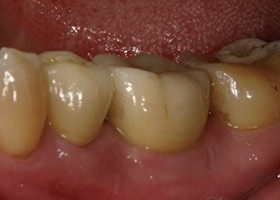

拔牙後傷口